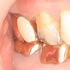

患者さんは20代女性

矯正中に来院して頂いた際には小さな虫歯だったのですが、

矯正が終わった頃には歯肉縁下まで入る大きな虫歯になってしまっていました。

それに伴い骨も大きく無くなっています。

矯正期間中に起りやすいリスクの1つ虫歯ですが、ここまで大きな虫歯・骨欠損を矯正の先生も気づかないものですかね!?(歯科医師の能力なので分からない先生は分からないのですが・・・)

今回のケースは、矯正治療で第2大臼歯も近心傾斜させてしまっており、上にレジンで立ち上げるスペースも無い為ヘミセクション(分割抜歯)を選択しました。